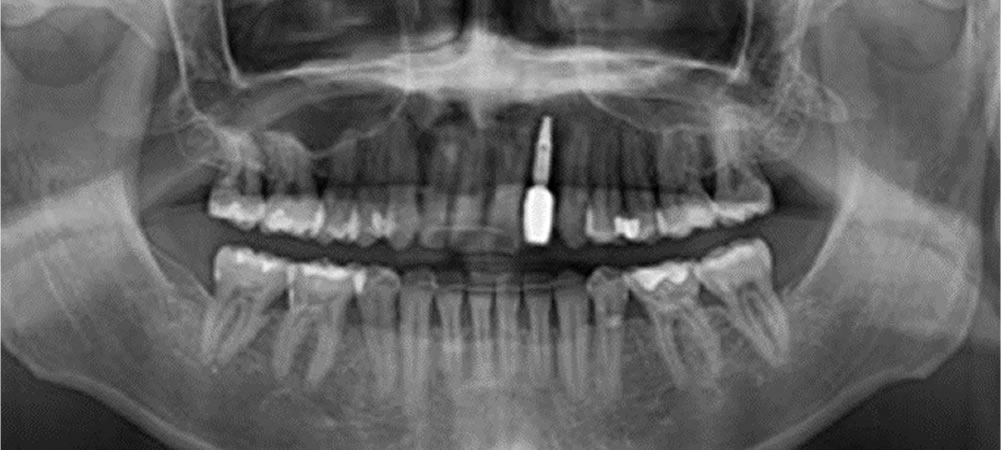

初診時のレントゲン画像

1歯の中間欠損の場合、補綴治療の選択肢としては義歯、ブリッジ、インプラント、接着ブリッジが挙げられます。患者さまは歯を削りたくないとのことから、インプラント治療を希望されました。中間欠損におけるインプラント治療は、両隣在歯の保護(切削量減、負担軽減)の観点から、第一選択と考えられます。

2回法を用いたインプラント治療を行う計画を立てました。

・一次手術でインプラント体を埋入し、歯槽骨とインプラント体が結合するのに4~6ヵ月待機します。

・二次手術で歯茎を作り、1~2ヵ月待機して印象採得を行い、補綴物を装着します。